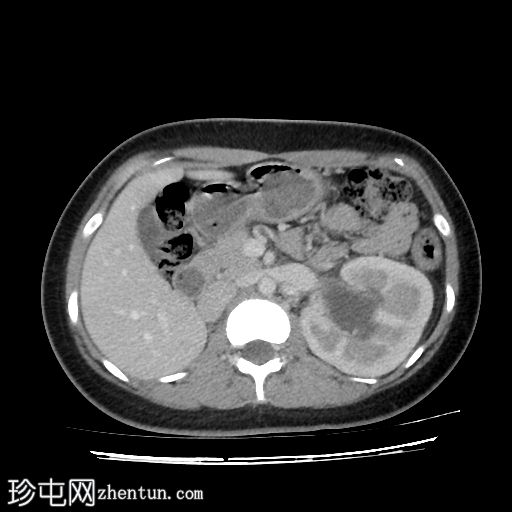

腹部CT平扫和造影扫描显示左肾实质增大,伴I级肾积水,右肾在肾窝内未见异常。双子宫完整(两个子宫体和两个宫颈),阴道隔膜将阴道分成两半,阴道右半部分积液,非造影片上积液密度较大,提示为

血液

(阴道积血)。

增强扫描图像提示存在一条血管分支压迫左肾盂-输尿管连接处,导致肾积水。

道格拉斯囊内有少量游离液体。

右侧卵巢可见黄体。

其他腹部器官未见异常。